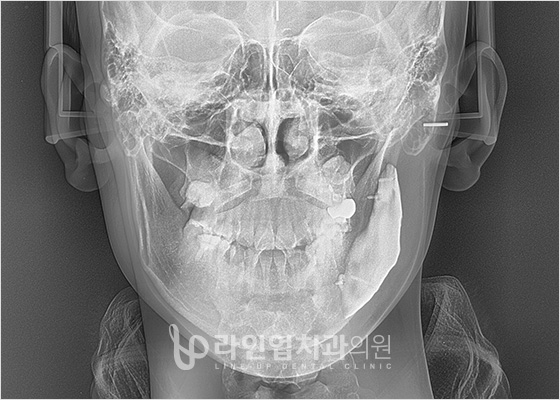

3D CT зураг авах

Өмнө ба дараах зураг

Before

After

3D Нарийвчлал оношлогооны систем

Энэ нь зөвхөн нүүрнтй яс төдийгүй үл үзэгдэх мэдрэл, цусны судасны байрлал, булчин, өөхний байдал, нүүрний яс, бүтэц, хөдөлгөөнийг төгс төгөлдөрт оношлодог.